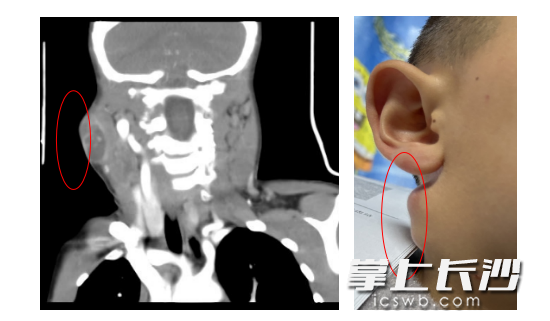

入院后,学生儿童结核科副主任、副主任医师周海依为患儿进行了仔细检查,发现其颈部有多发淋巴结肿大,右下颌处有一直径约3厘米的包块,表面红肿破溃,按压有波动感;左侧有3个包块,最大的直径2.5厘米左右。经过进一步完善检查,认为结核病诊断依据不足,联合耳鼻咽喉头颈外科副主任、主任医师周定刚会诊,明确有手术指征,转耳鼻咽喉头颈外科,进行双侧颌下淋巴结清扫术+皮瓣修整术。